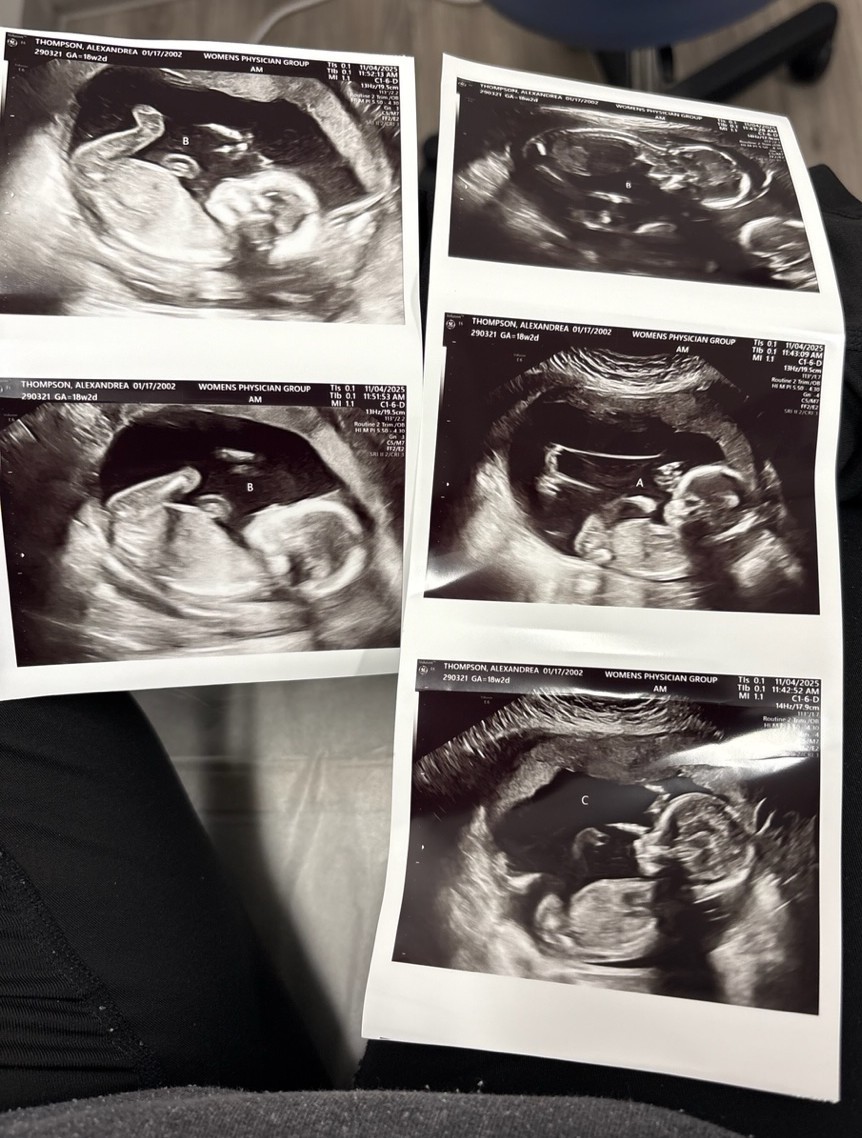

The two men had a recent milestone in their pro-life work with ministering to a pregnant mom who is carrying triplets.

Mom Alex was leaving Planned Parenthood in Carbondale, Ill., with a friend driving recently when Hamman called out from the sidewalk to them to see if he could be of service. Alex said she was keeping her babies after it had been revealed she was pregnant with triplets due to arrive in the spring of 2026.

After Hammans connected Alex with Lewis, Lewis was able to secure an ultrasound appointment for her. That appointment was Lewis’s first meeting with the expectant mom, and they remain in contact as his organization continues to help meet her needs, which has included help with rent and groceries.